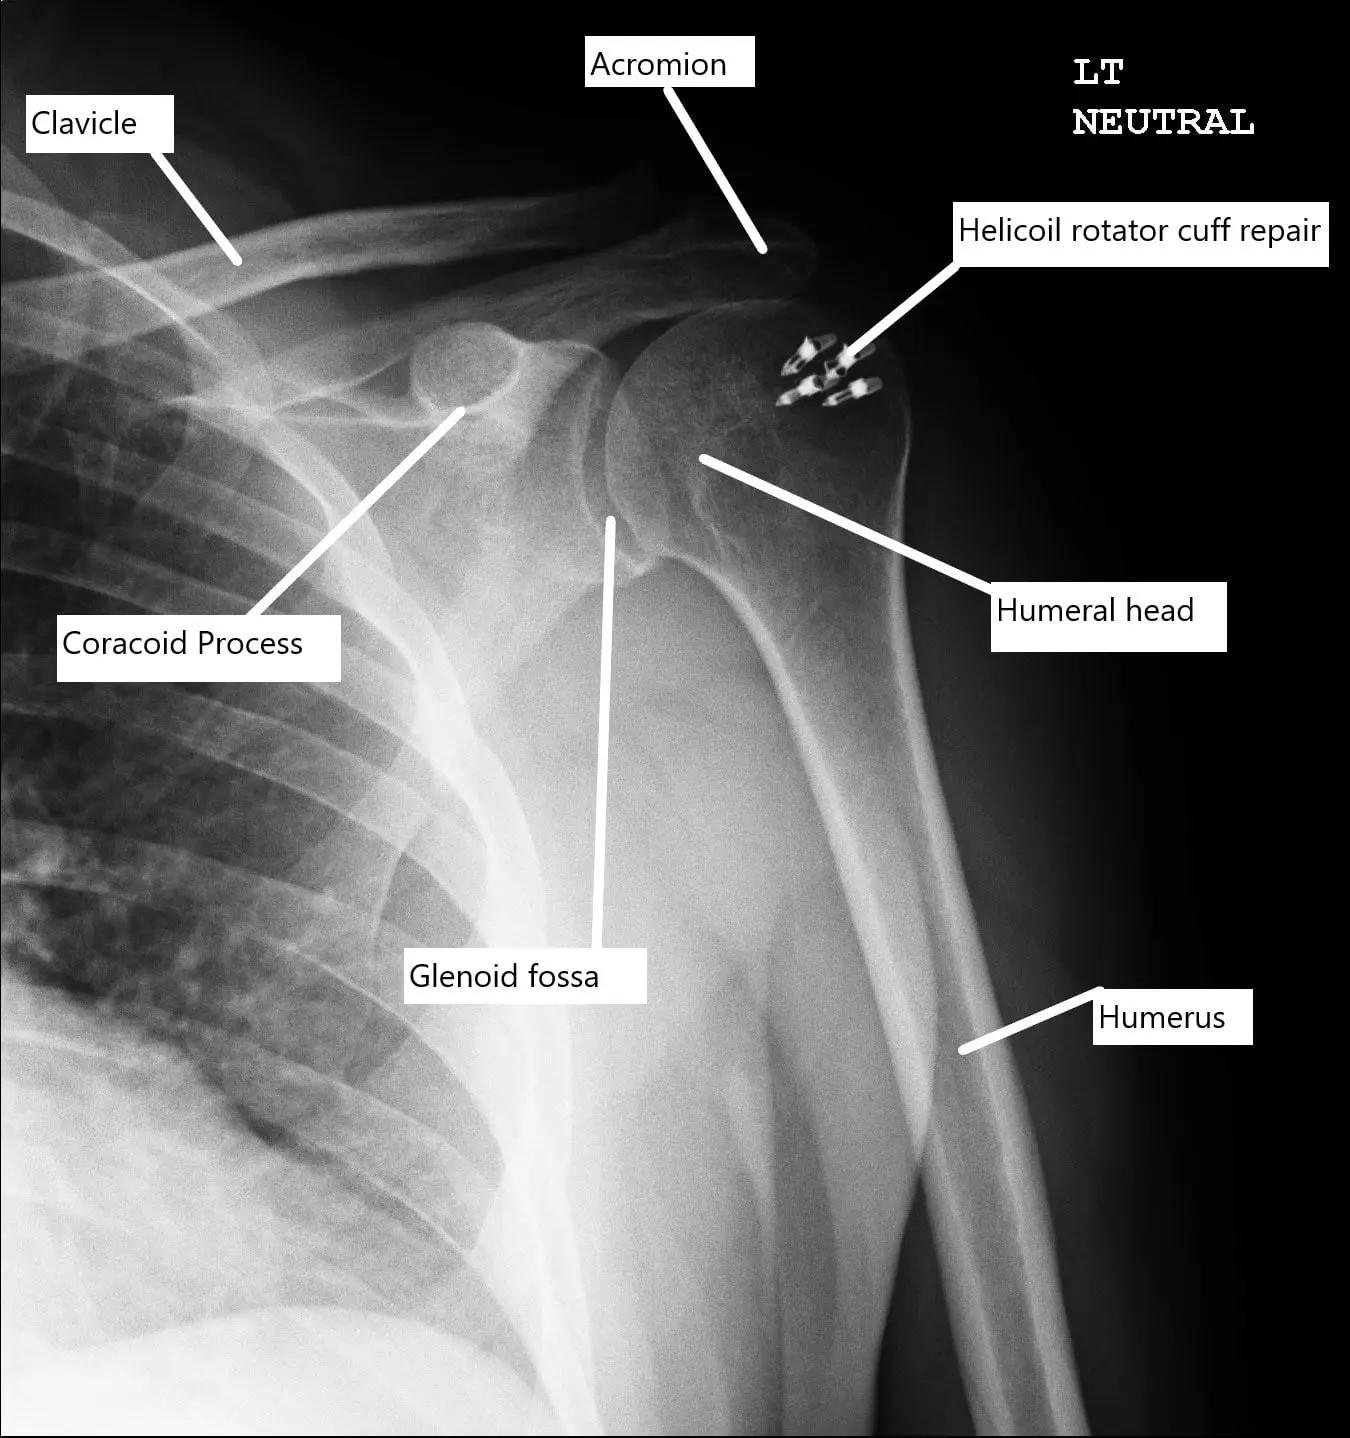

Postoperative X-ray of the shoulder with rotator cuff repair.

Acromioplasty was performed by removing the anterolateral acromial spur and as well as the inferior surface of anterior 2/3rd of the acromion. A decision was made to repair the rotator cuff. An accessory lateral portal was made. The footprint for the rotator cuff was debrided using a burr exposing the subcortical bone.

Then, a 4.5 mm Helicoil (S&N) with four tails was used and inserted into the humeral head following drilling and tapping. All the four tails were passed through the rotator cuff sequentially from the anterior to the posterior edge. The tails were tied over each over on to itself using a sliding knot.

The rotator cuff was well opposed. Final pictures were taken and saved. The shoulder was irrigated and drained.